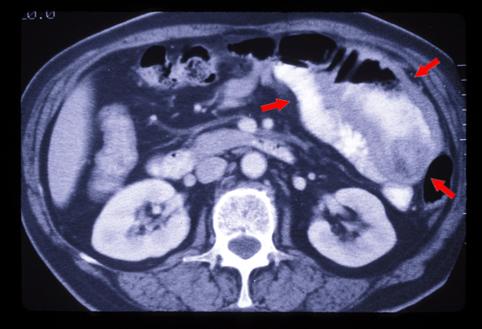

伴有明显肠壁肥厚的原发性B型小肠恶性淋巴瘤(国立癌中心东医院<关口隆三&lgt;和九州癌中心共同做成)

恶性淋巴系肿瘤/恶性淋巴瘤

小肠/空肠

CT

40以上

s(a)